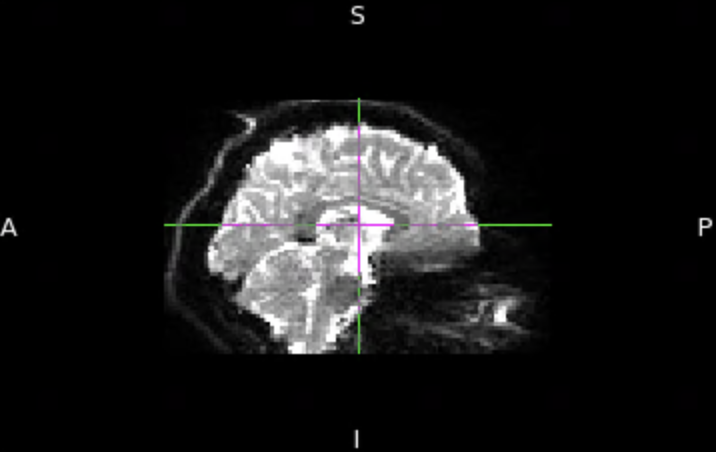

Posterior to Anterior Flip

For some reason, my DWI output from DTIPrep is flipped

posterior-to-anterior (see attached image). I have confirmed that